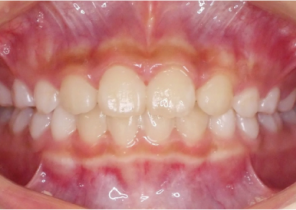

Informe de caso 2

7 años, 11 meses de edad, 24 etapas con dispositivos Invisalign Palatal Expander

Cortesía del Dr. David R. Boschken

Antes de la disyunción con el sistema Invisalign Palatal Expander

Después de la disyunción con el sistema Invisalign Palatal Expander

Después del tratamiento con el sistema Invisalign Palatal Expander